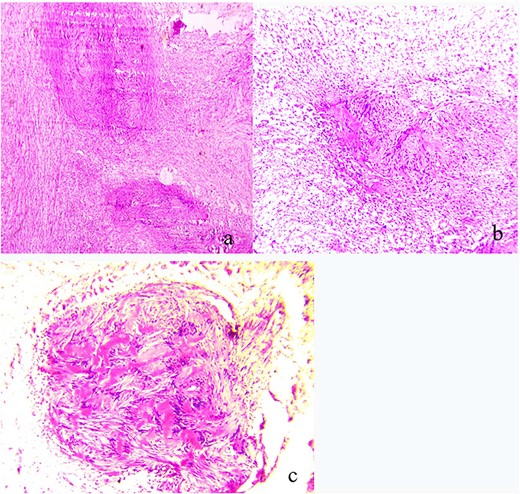

The patient underwent surgical excision with a transcervical approach. Intra-operatively, the mass was found lying medial to the CCA, the ICA and the ECA. The vagus nerve was visualized running over the top of the mass, uninvolved in the tumor formation (Fig. 2). Instead, the cervical sympathetic chain was identified superiorly and inferiorly to the mass, making CSCS the most likely diagnosis. Resection was performed with dissection and preservation of the vagus nerve. The Horner’s syndrome was observed in the left eye after surgical excision. Pathology reports showed plexiform schwannoma, including Antoni A and Antoni B areas with Verocay bodies (Fig. 3).

(a) Pathologic findings demonstrating plexiform schwannoma; (b) both Antoni A and Antoni B areas; (c) Verocay bodies.